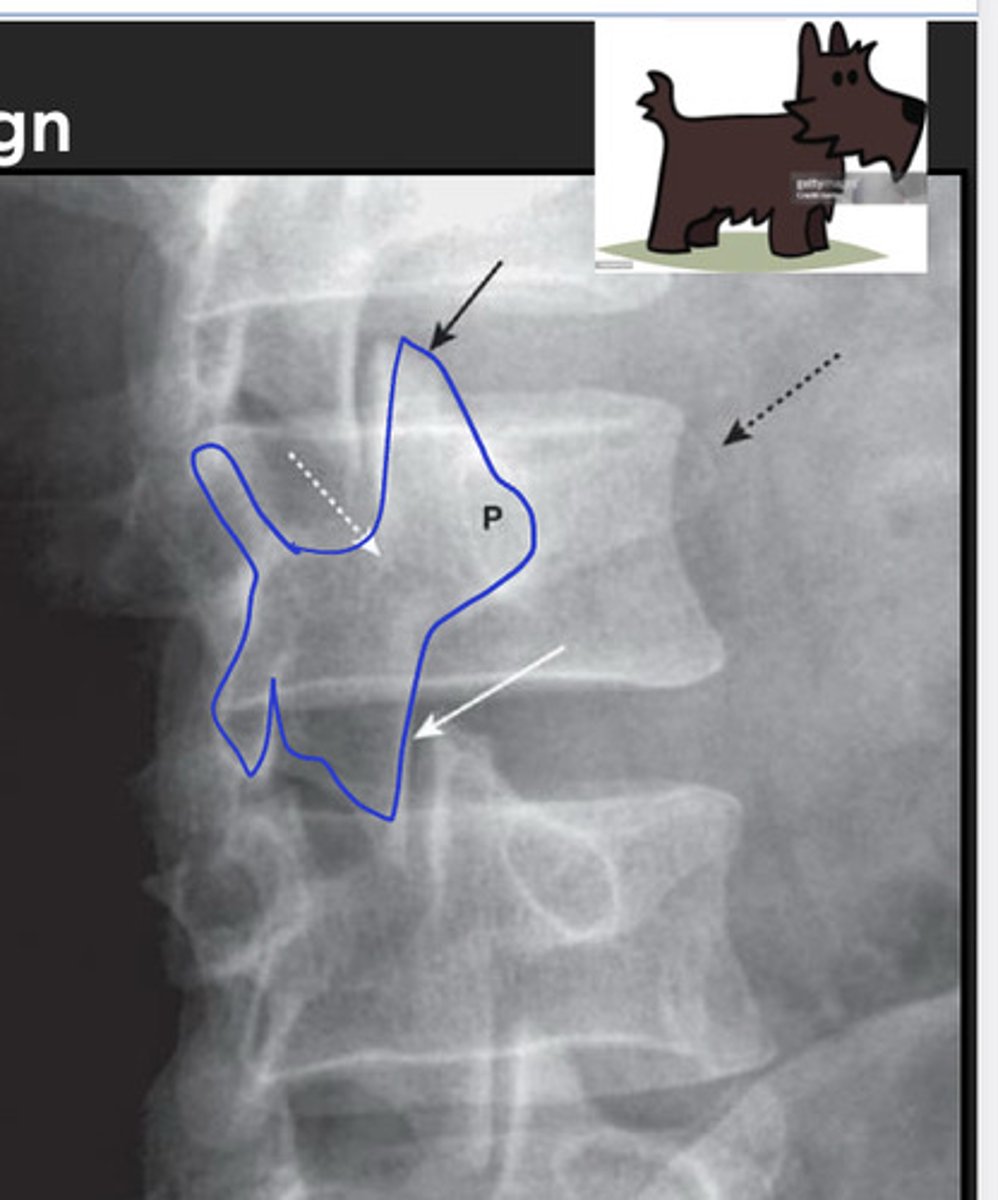

scottie dog sign

seen on oblique views; "the best dog in medicine"